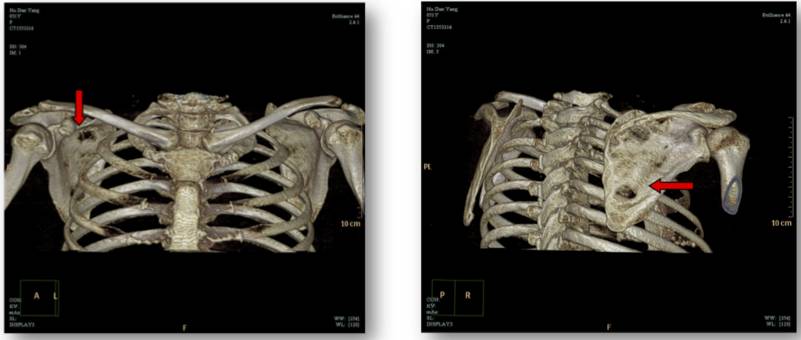

图一:2016-11-19 肩胛骨CT平扫+三维重建:右侧肩胛骨多发骨质破坏。

我们对胡女士的病情进行了MDT讨论,考虑到胡女士目前骨痛症状严重,并且辅助内分泌治疗不足两年,可能存在原发内分泌耐药的情况,讨论决定给予她NP方案及唑来膦酸的治疗。经历了4个周期的化疗,她的骨痛情况明显好转,恢复正常行走,肩胛骨CT平扫+三维重建提示右侧肩胛骨骨质破坏较前好转。但此时胡女士已无法耐受化疗的各种不良反应,提出停止化疗的要求。

图二:2017.3.8肩胛骨CT平扫+三维重建:右侧肩胛骨骨质破坏较前好转。